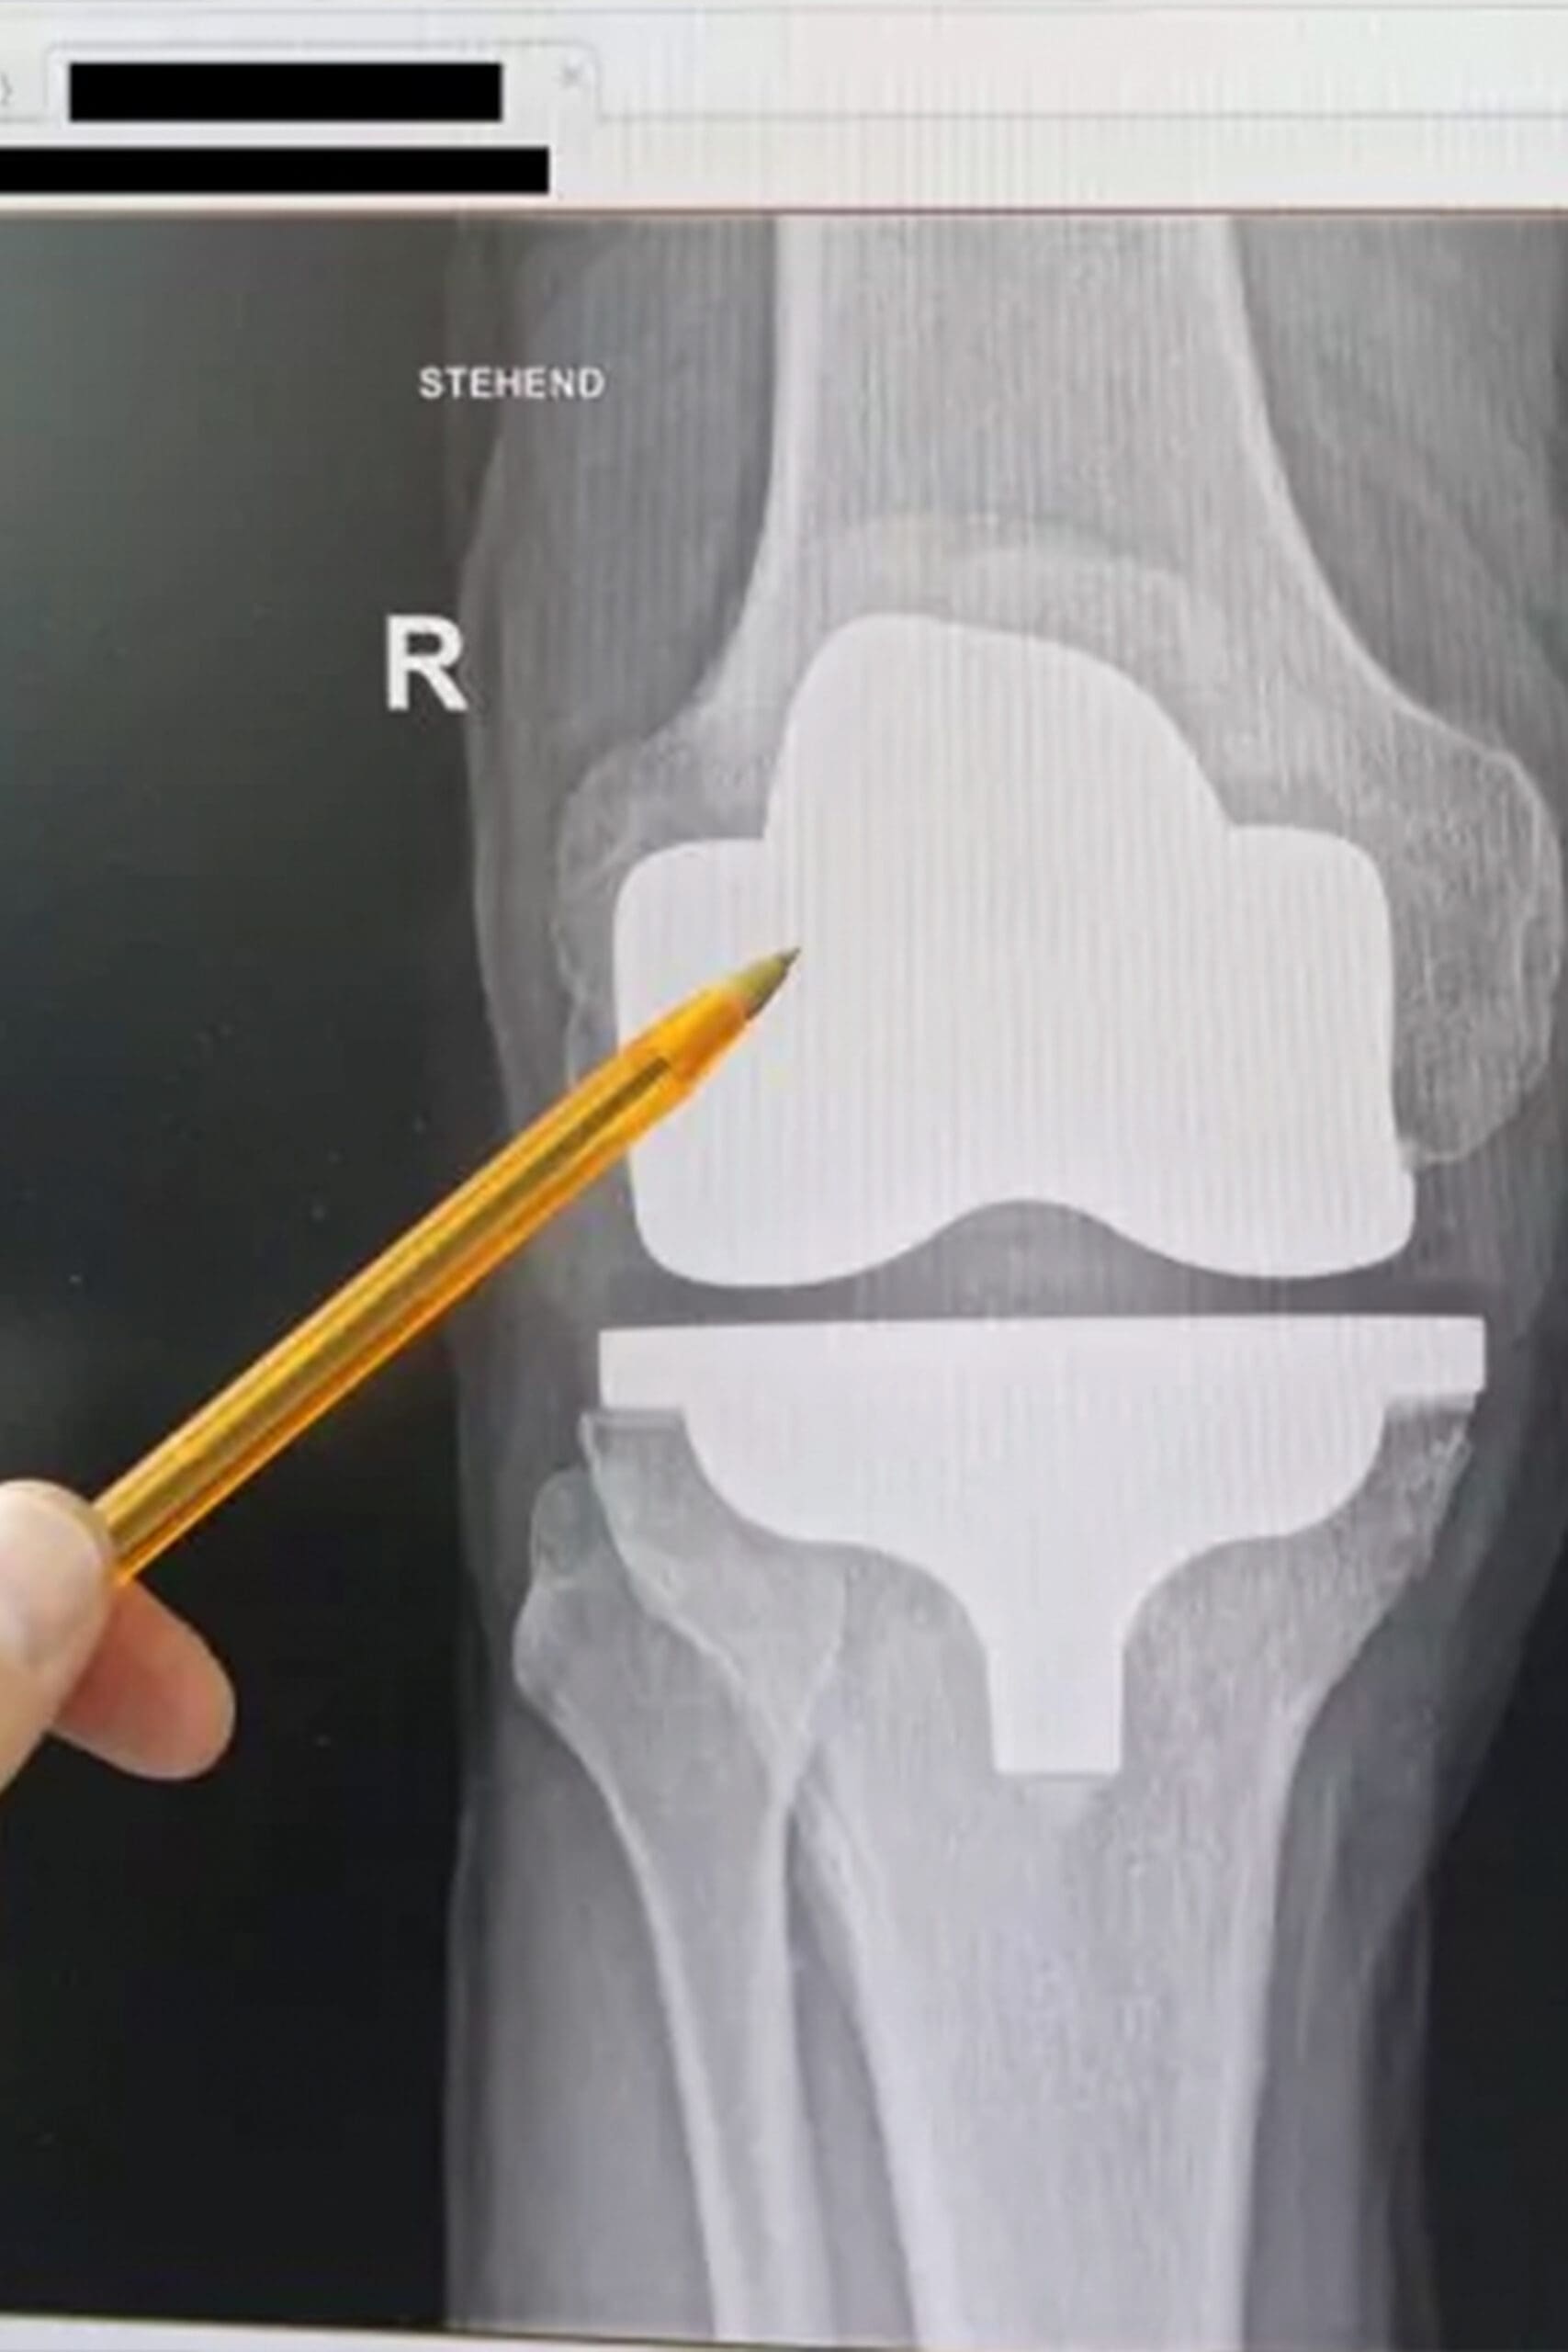

Wie sind Prothesen aufgebaut und wie lange halten sie?

Prothesen bestehen aus einem Schaft zur Befestigung und einem funktionellen Teil. Interne Prothesen (Endoprothesen) wie Hüftprothesen oder Knieprothesen werden im Knochen verankert und ahmen die Gelenkfunktion nach. Sie bestehen meist aus Titan, Kunststoff (z.B. Polyethylen) oder Keramik. Moderne Prothesen sind nicht magnetisch und somit MRT-tauglich. Ältere Modelle könnten magnetisch sein, was eine MRT-Untersuchung beeinträchtigen kann. Ein Prothesenpass dokumentiert Material, Anpassungen und Operationen, was für die medizinische Betreuung wichtig ist.